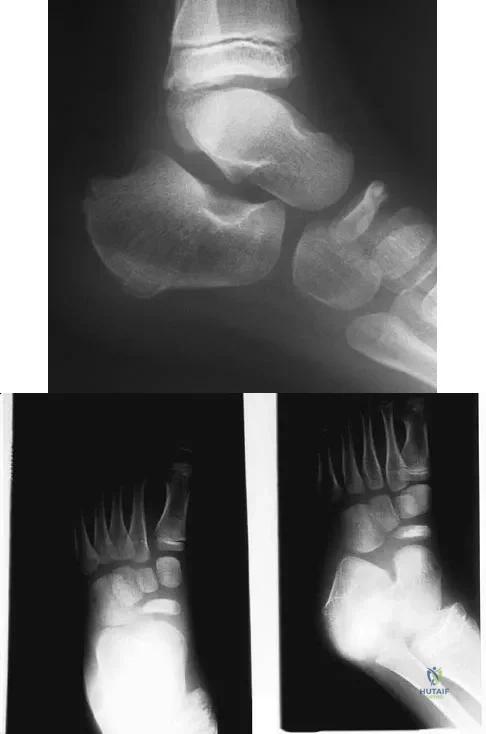

Question 51

Figures 5a and 5b show the radiographs of a 56-year-old man who was seen in the emergency department following a twisting injury to his left ankle. Examination in your office 3 days later reveals marked swelling and diffuse tenderness to palpation about the ankle and leg. What is the next most appropriate step in management?

Explanation